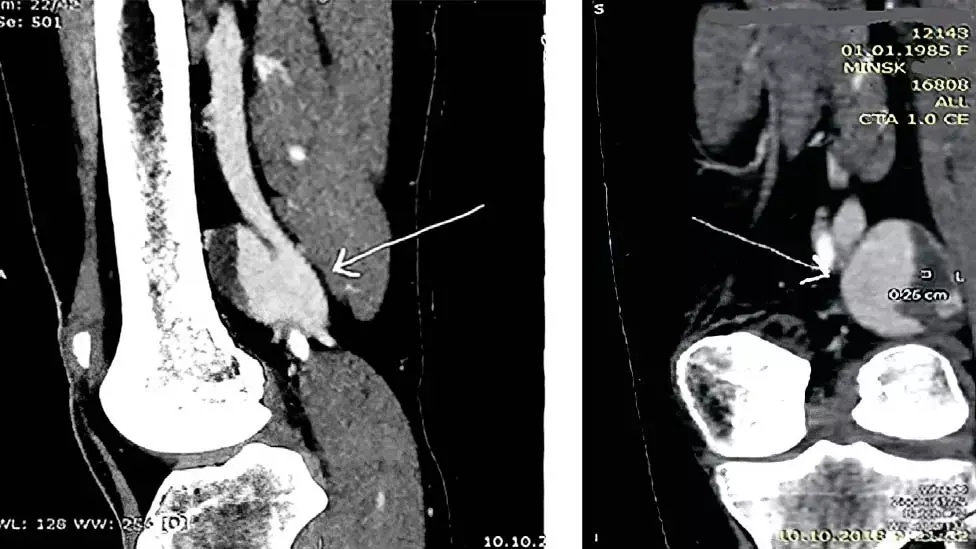

Рисунок 1. УЗ-верификация аневризмы подколенной вены.Основным методом диагностики аневризмы подколенной вены является ультразвуковая верификация, позволяющая выявить патологию на ранних этапах, оценить диаметр подколенной вены, ее анатомические изменения и характер кровотока (см. рис. 1).

— В качестве дополнительного метода диагностики (для выработки хирургического подхода, детализации патологии) используется КТ- или МР-ангиофлебография, — объясняет Иван Климчук. — Безусловным плюсом данного метода является возможность одномоментной оценки русла легочной артерии с целью подтверждения либо исключения ТЭЛА.

В ходе гематологического обследования выявлена гетерозиготная тромбофилия, ассоциированная с высоким уровнем VIII фактора свертывания крови и наследственным дефицитом XII фактора свертывания крови со вторичной недостаточностью фибринолиза. Во время третьей госпитализации по поводу рецидива ТЭЛА в ходе выполнения ультразвукового исследования вен нижних конечностей пациентка из положения лежа переводится в ортостаз и выявляется мешковидная аневризма подколенной вены с грибовидным выступом 29×34 мм (лежа — 15 мм) с пристеночным тромбообразованием. Дообследуют пациентку с помощью КТ-флебографии, которая детализирует хирургическую анатомию аневризмы (см. рис. 2). Подтверждается пристеночный тромбоз аневризматического мешка.